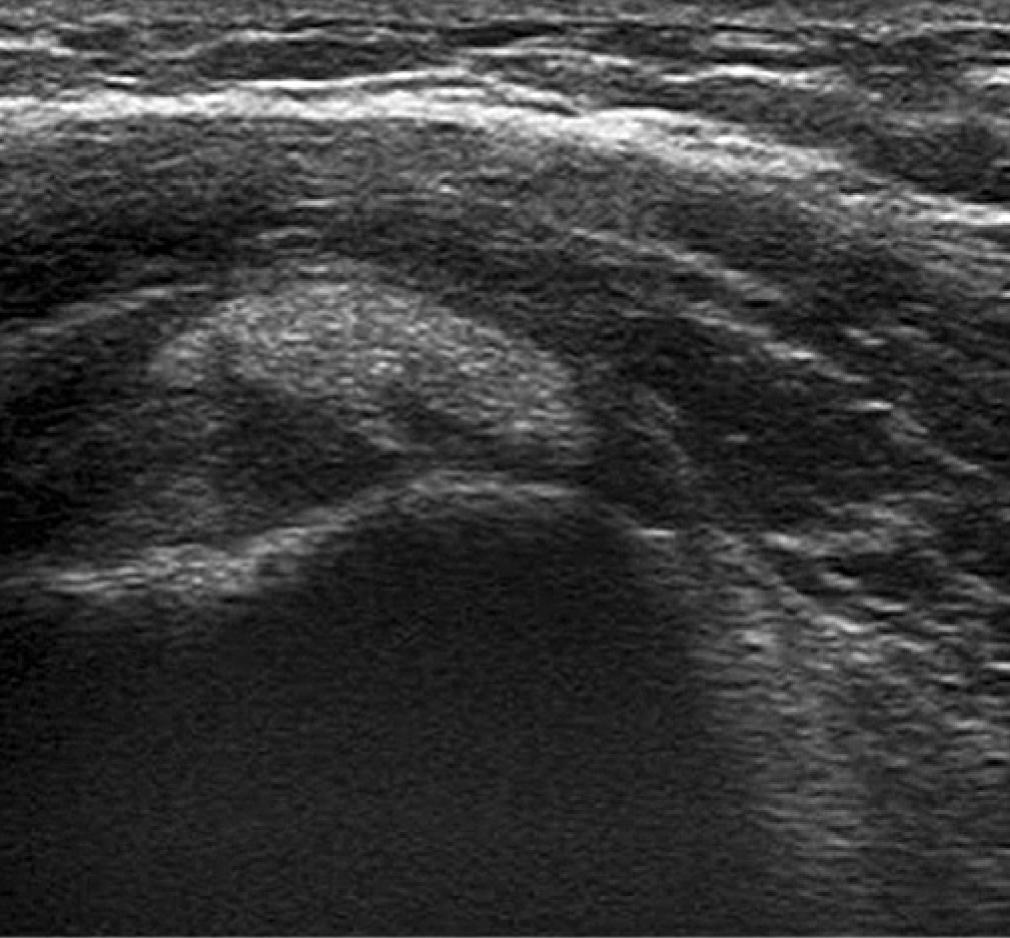

Often this diagnosis is obvious as the patient cannot externally rotate the shoulder for visualization of the subscapularis tendon. There is often a small amount of fluid in the long head of biceps tendon sheath which reflects the small glenohumeral joint effusion that is present (Fig. 7 and Fig. 8).

Fluid in the long head of biceps tendon sheath and the subdeltoid subacromial bursa – transverse view. There is a vessel visible (a branch of the anterior humeral circumflex artery) but no neovascularization

Fluid in the long head of biceps tendon sheath and the subdeltoid subacromial bursa – longitudinal view